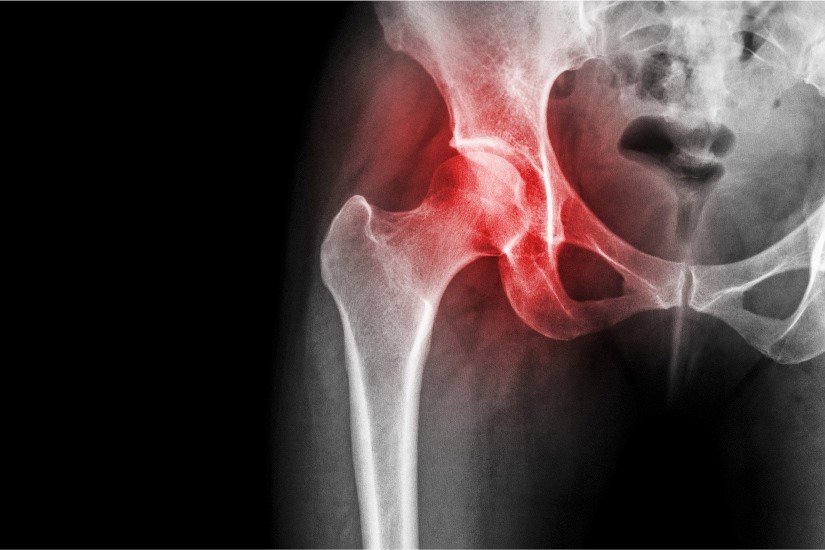

Pacientul s-a prezentat cu dureri la nivelul șoldului care limitau mișcarea, simptome care pot fi confundate uneori cu alte patologii musculare. Diagnosticul de sindrom de impingement femuroacetabular, specific persoanelor tinere cu varsta mai mica de 45 de ani, este un precursor al coxartrozei. Solutia clasica este artroplastia de sold (protezarea soldului) ceea ce inseamna inlocuirea articulatiei soldului cu un implant artificial. In cazul de fata era vorba despre formarea de osteofite in jurul colului femural si al acetabulului (cavitatea articulara a osului coxal care „prinde” capul femurului) avand ca efect durerea si diminuarea mobilitatii soldului, dar cu pastrarea integritatii cartilaginoase a articulatiei.

„Printr-o interventie artroscopica minim invazivă, respectiv patru incizii de cativa milimetri, s-a realizat excizia osteofitelor si restabilirea functiei articulare. Avantajele sunt certe: o recuperare rapida de cateva saptamani, amanarea protezarii cu cel putin 15 ani - care probabil va fi necesara la un moment dat, o reala imbunatatire a functiei si redobandirea mobilitatii, cu disparita durerii. Interventia implica riscuri aproape zero, post-operator nu exista contraindicatii, asa cum exista in cazul protezei de sold, unde recuperarea este lenta si dificila”, a spus dr. George Ovidiu Muntean

- artroscopia de sold este o interventie chirurgicala minim-invaziva, articulatia fiind abordata prin 3-4 microincizii milimetrice la nivelul soldului afectat prin care se vizualizeaza compartimentele articulare cu ajutorul unui telescop. Imaginea obtinuta este marita, proiectata pe un monitor, iar medicul chirurgul ortoped vede statusul articulatiei si poate rezolva leziunile intraarticulare, de la remodelarea capului femural sau a cupei acetabulare, pana la extragerea de resturi de cartilaj, corpi liberi articulari, lavaj articular si altele.

O alta diferenta majora este ca prin artroscopie si remodelarea articulara (osteoplastie, asa cum a fost si in cazul prezentat) se previne sau se amana cu multi ani necesitatea unei protezari, iar facuta la timp poate salva de o posibila proteza articulara. Sindromul de impingement femuroacetabular, remodelarea jonctiunii col-cap femural sau osteoplastia capului femural se califica perfect pentru rezolvare prin artroscopie.